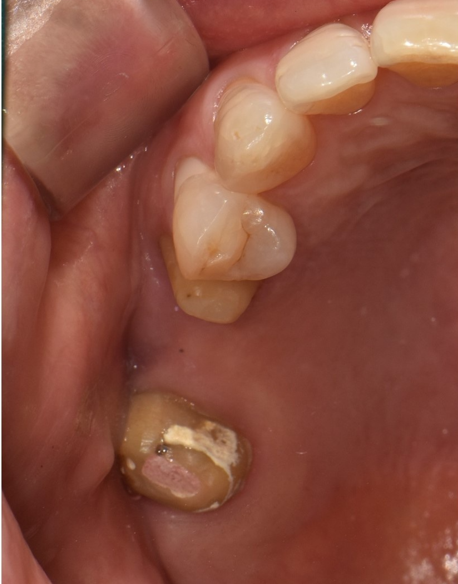

60대 여성 환자분은 오른쪽 위에 오래전에 제작한 브릿지가 완전히 탈락한 상태로 내원하셨습니다.

브릿지로 오랜 시간 버티는 동안, 양쪽 지대치(브릿지를 지탱하던 치아)가 심하게 손상되어 있었습니다.

더 큰 문제는 잇몸뼈였습니다.

치아가 없는 상태로 오래 방치되면서, 잇몸뼈가 상당 부분 흡수되어 있었습니다.

"최대한 버티자"는 생각이, 결과적으로 치료를 더 어렵게 만들었습니다.

임플란트를 식립하기 위해서는 충분한 잇몸뼈가 필요한데, 이미 뼈가 많이 소실된 상태였죠.

결국 뼈 이식을 포함한 복잡한 치료 과정을 거쳐야 했고, 치료 기간도 9개월이 소요되었습니다.